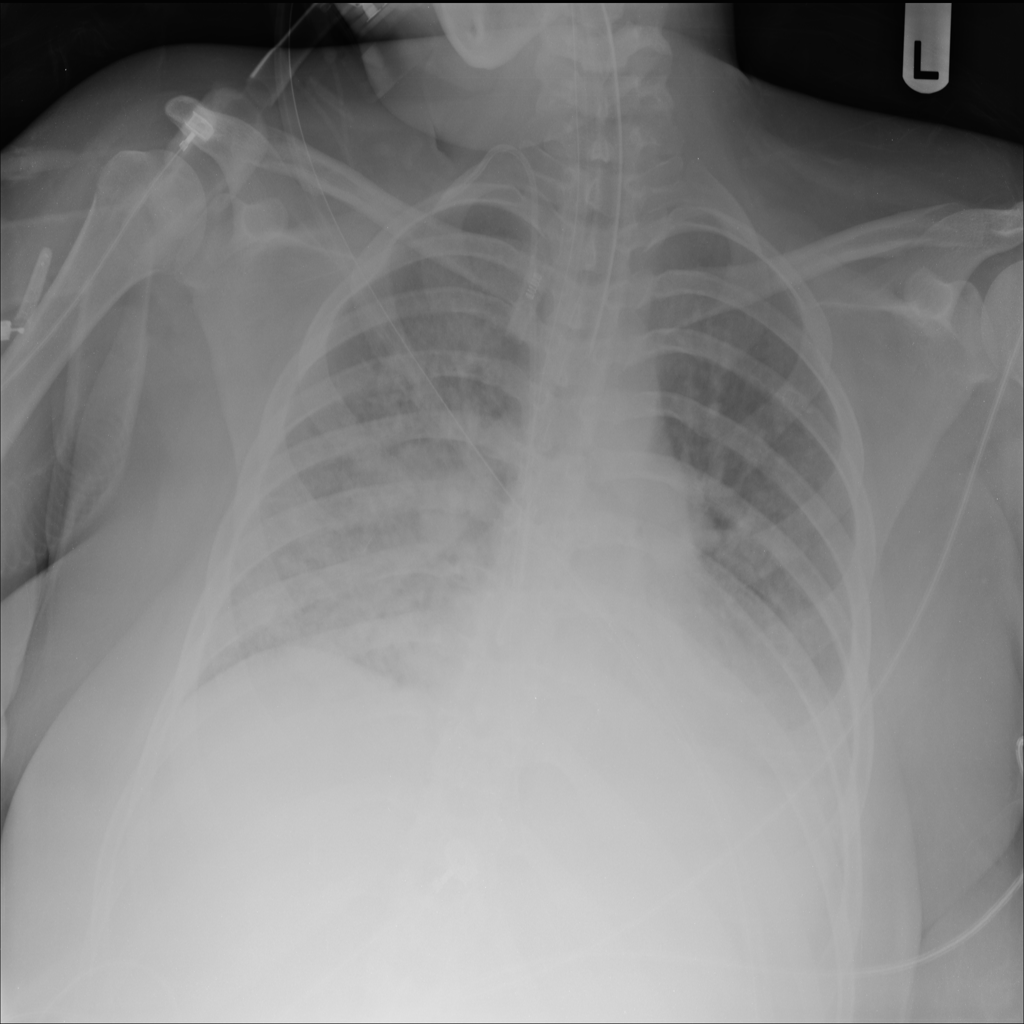

PAT-EBE1 · IMG-019Pneumonia

PAT-EBE1 · IMG-019

AP